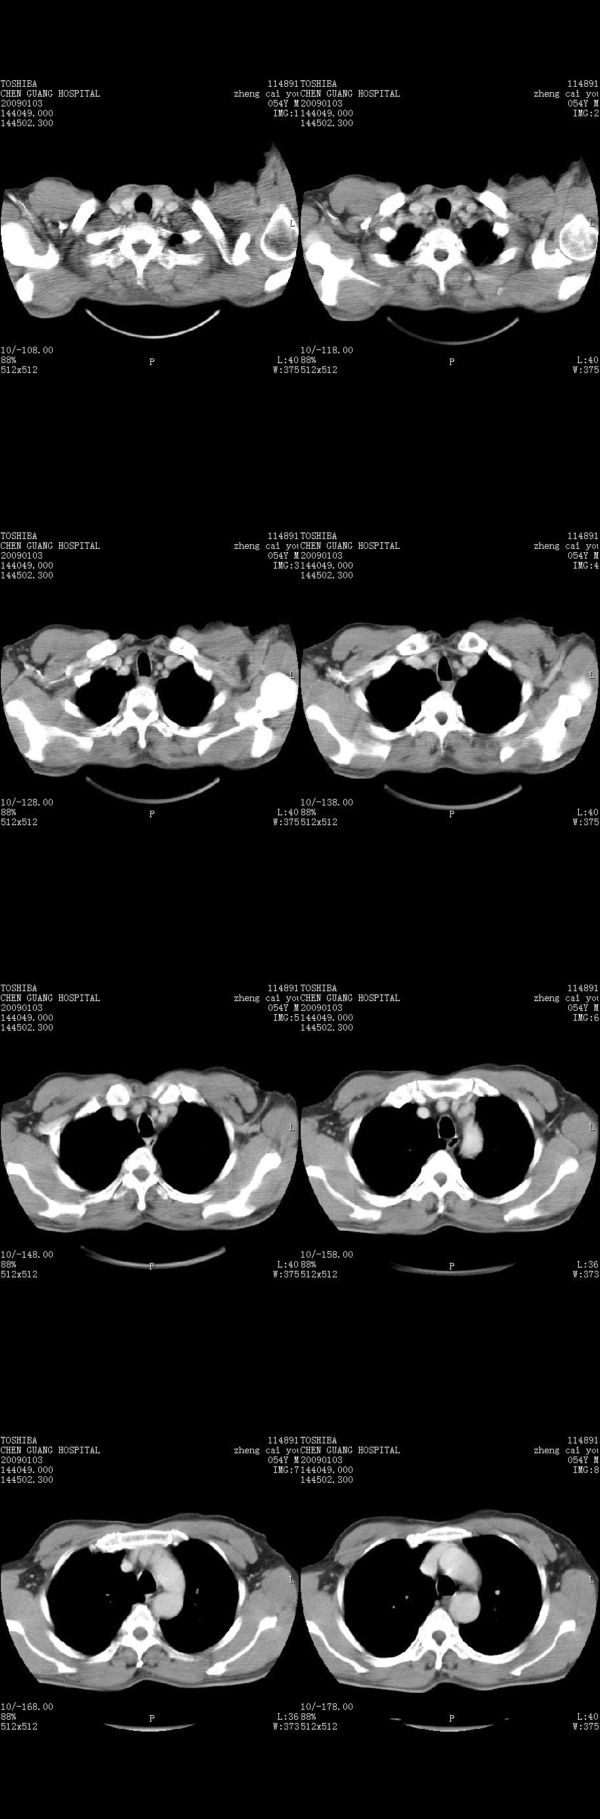

男,54岁,右侧胸部疼痛,平时吸烟,有抽烟后咳嗽咯痰史。昨天没把xiphoid软件吃懂,所以没把纵隔窗图像处理出来!请各位老师帮忙看一下右肺门有没有问题?谢谢!!!!!!!!!!

右肺上叶后段近气管旁仍可见一结节灶,不除外为肿大的淋巴结影。

我同学讲红线部分强化不好,感觉不是很舒服,这是什么道理?

我同学讲红线部分强化不好,感觉不是很舒服,应该 是软组织间隙,不是一个孤立的病灶。

气管前腔静脉后似见增大淋巴结影,肺门区未见明显肿块影。肺窗示右肺中叶外侧段透亮度增高,可过一段时间再查一下对比一下,毕竟是自己的至亲,又有条件,辐射就顾不得了。

也觉得还好吧,只是右下肺动脉显粗了点,纵膈有钙化淋巴结,再有肺窗就更好了

各位老师:奇静脉增宽,肺上未见明显实变,这还需注意观察些什么?????